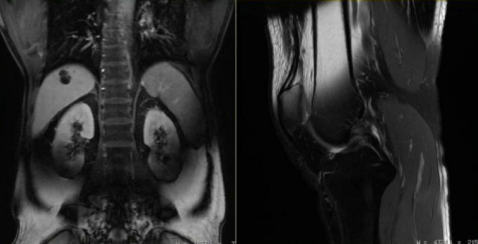

图像清晰,尤其适合检查脑部、脊椎、韧带、肌肉、肿瘤等软组织

这些信号被机器接收,再经过电脑处理,就可以“拼”出一张非常清晰的人体内脏、骨骼、肌肉等组织的图像。

金属干扰图像,医生可能看不清病灶

金属物会扭曲磁场,就像在平静的湖面扔石头,导致图像出现漩涡状伪影,重要病灶可能被完全掩盖。

图/杭州日报